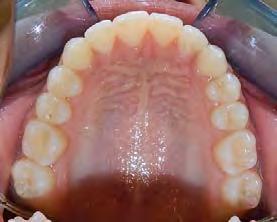

Se presenta una paciente de 13 años 5 meses con el motivo de consulta “es que no me baja el colmillo”. En los estudios extraorales se ve el perfil concavo y labios en contacto durante el reposo (Figura 1). En los estudios intraorales tenemos , clase I esquelética, con crecimiento hipodivergente (Figura 2), clase II molar derecha y clase I molar y canina izquierda, la clase canina derecha no determinada

Figura 1. Perfil, frente en reposo, sonrisa.

(ND), órgano dental (OD) 13 retenido, mordida abierta en sectores laterales, overjet de 3 mm y overbite de 10%, líneas medias dentales desviadas y microdoncia de OD 12 y 22.

En la oclusal superior vemos la forma de la arcada que es oval con apiñamiento leve (Figura 4) y la inferior es cuadrada.

Figura 4. Vista oclusal superior e inferior.